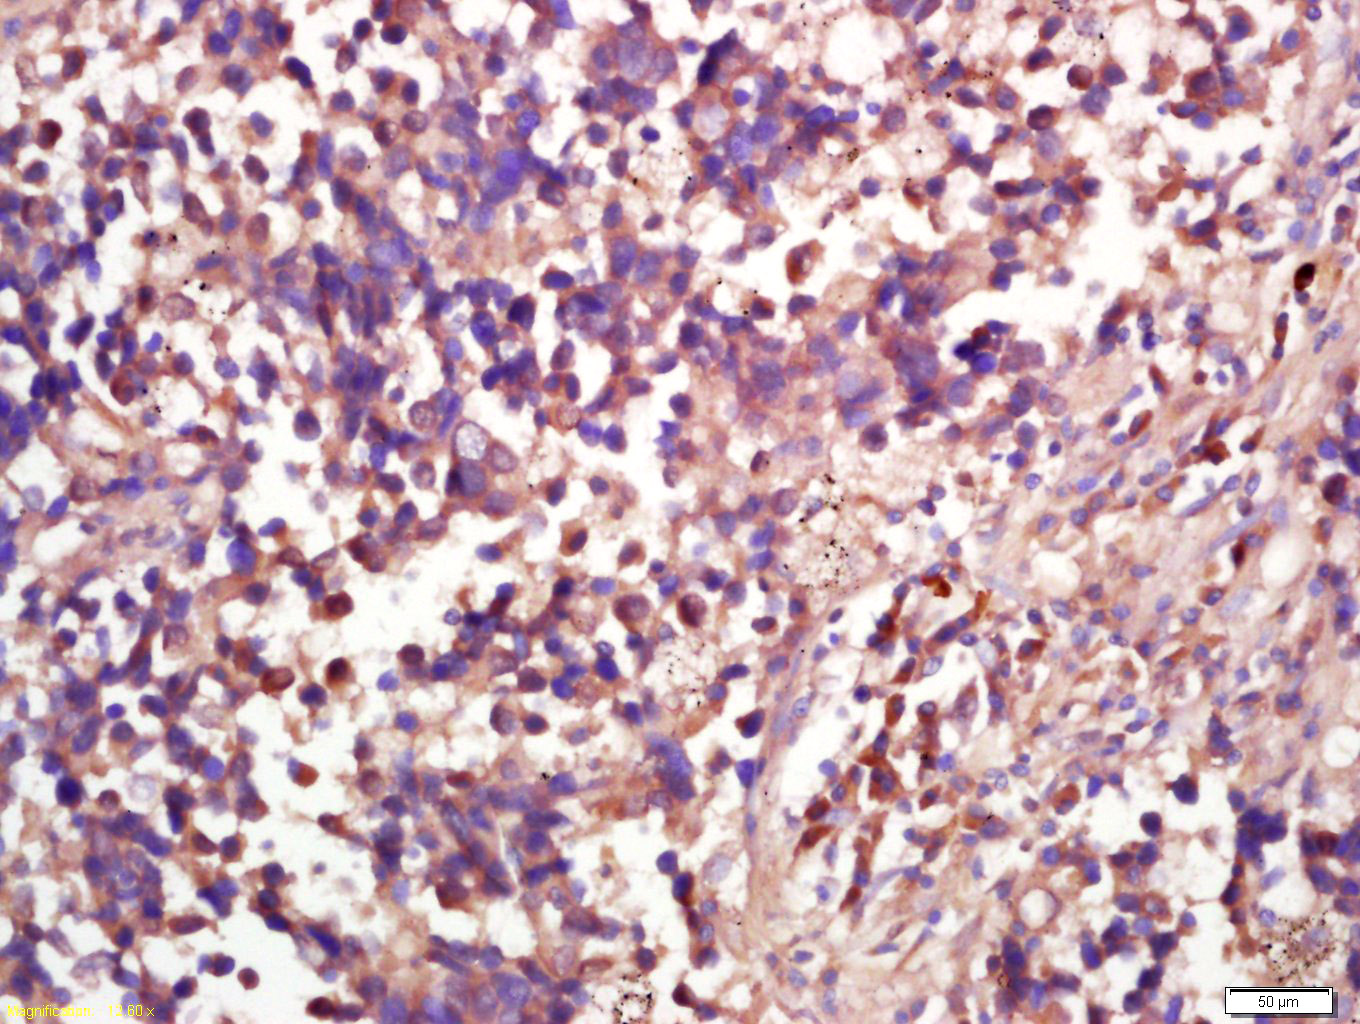

Tissue/cell: human lung carcinoma; 4% Paraformaldehyde-fixed and paraffin-embedded; Antigen retrieval: citrate buffer ( 0.01M, pH 6.0 ), Boiling bathing for 15min; Block endogenous peroxidase by 3% Hydrogen peroxide for 30min; Blocking buffer (normal goat serum,C-0005) at 37℃ for 20 min; Incubation: Anti-Rsk2 Polyclonal Antibody, Unconjugated(bs-3554R) 1:200, overnight at 4°C, followed by conjugation to the secondary antibody(SP-0023) and DAB(C-0010) staining

Tissue/cell: rat brain tissue; 4% Paraformaldehyde-fixed and paraffin-embedded; Antigen retrieval: citrate buffer ( 0.01M, pH 6.0 ), Boiling bathing for 15min; Block endogenous peroxidase by 3% Hydrogen peroxide for 30min; Blocking buffer (normal goat serum,C-0005) at 37℃ for 20 min; Incubation: Anti-Rsk2 Polyclonal Antibody, Unconjugated(bs-3554R) 1:200, overnight at 4°C, followed by conjugation to the secondary antibody(SP-0023) and DAB(C-0010) staining